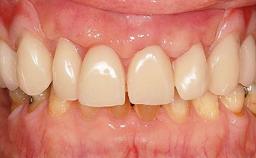

Fixed and removable prosthodontic implant therapy for restoration of the edentulous maxilla is both complex and challenging. Careful assessment and planning is needed in each individual case to explore whether a fixed or a removable solution will be the more suitable to satisfy the patient’s preference for optimal esthetics, phonetics, comfort and function. This Learning Pathway explores the prosthodontically driven treatment planning based on structured assessment, considered diagnosis and practical application in clinical case examples.

Edentulous Maxilla Fixed vs. Removable Prosthodontics Planning Principles Prosthodontic Planning & Procedures Prosthodontic Planning & Procedures